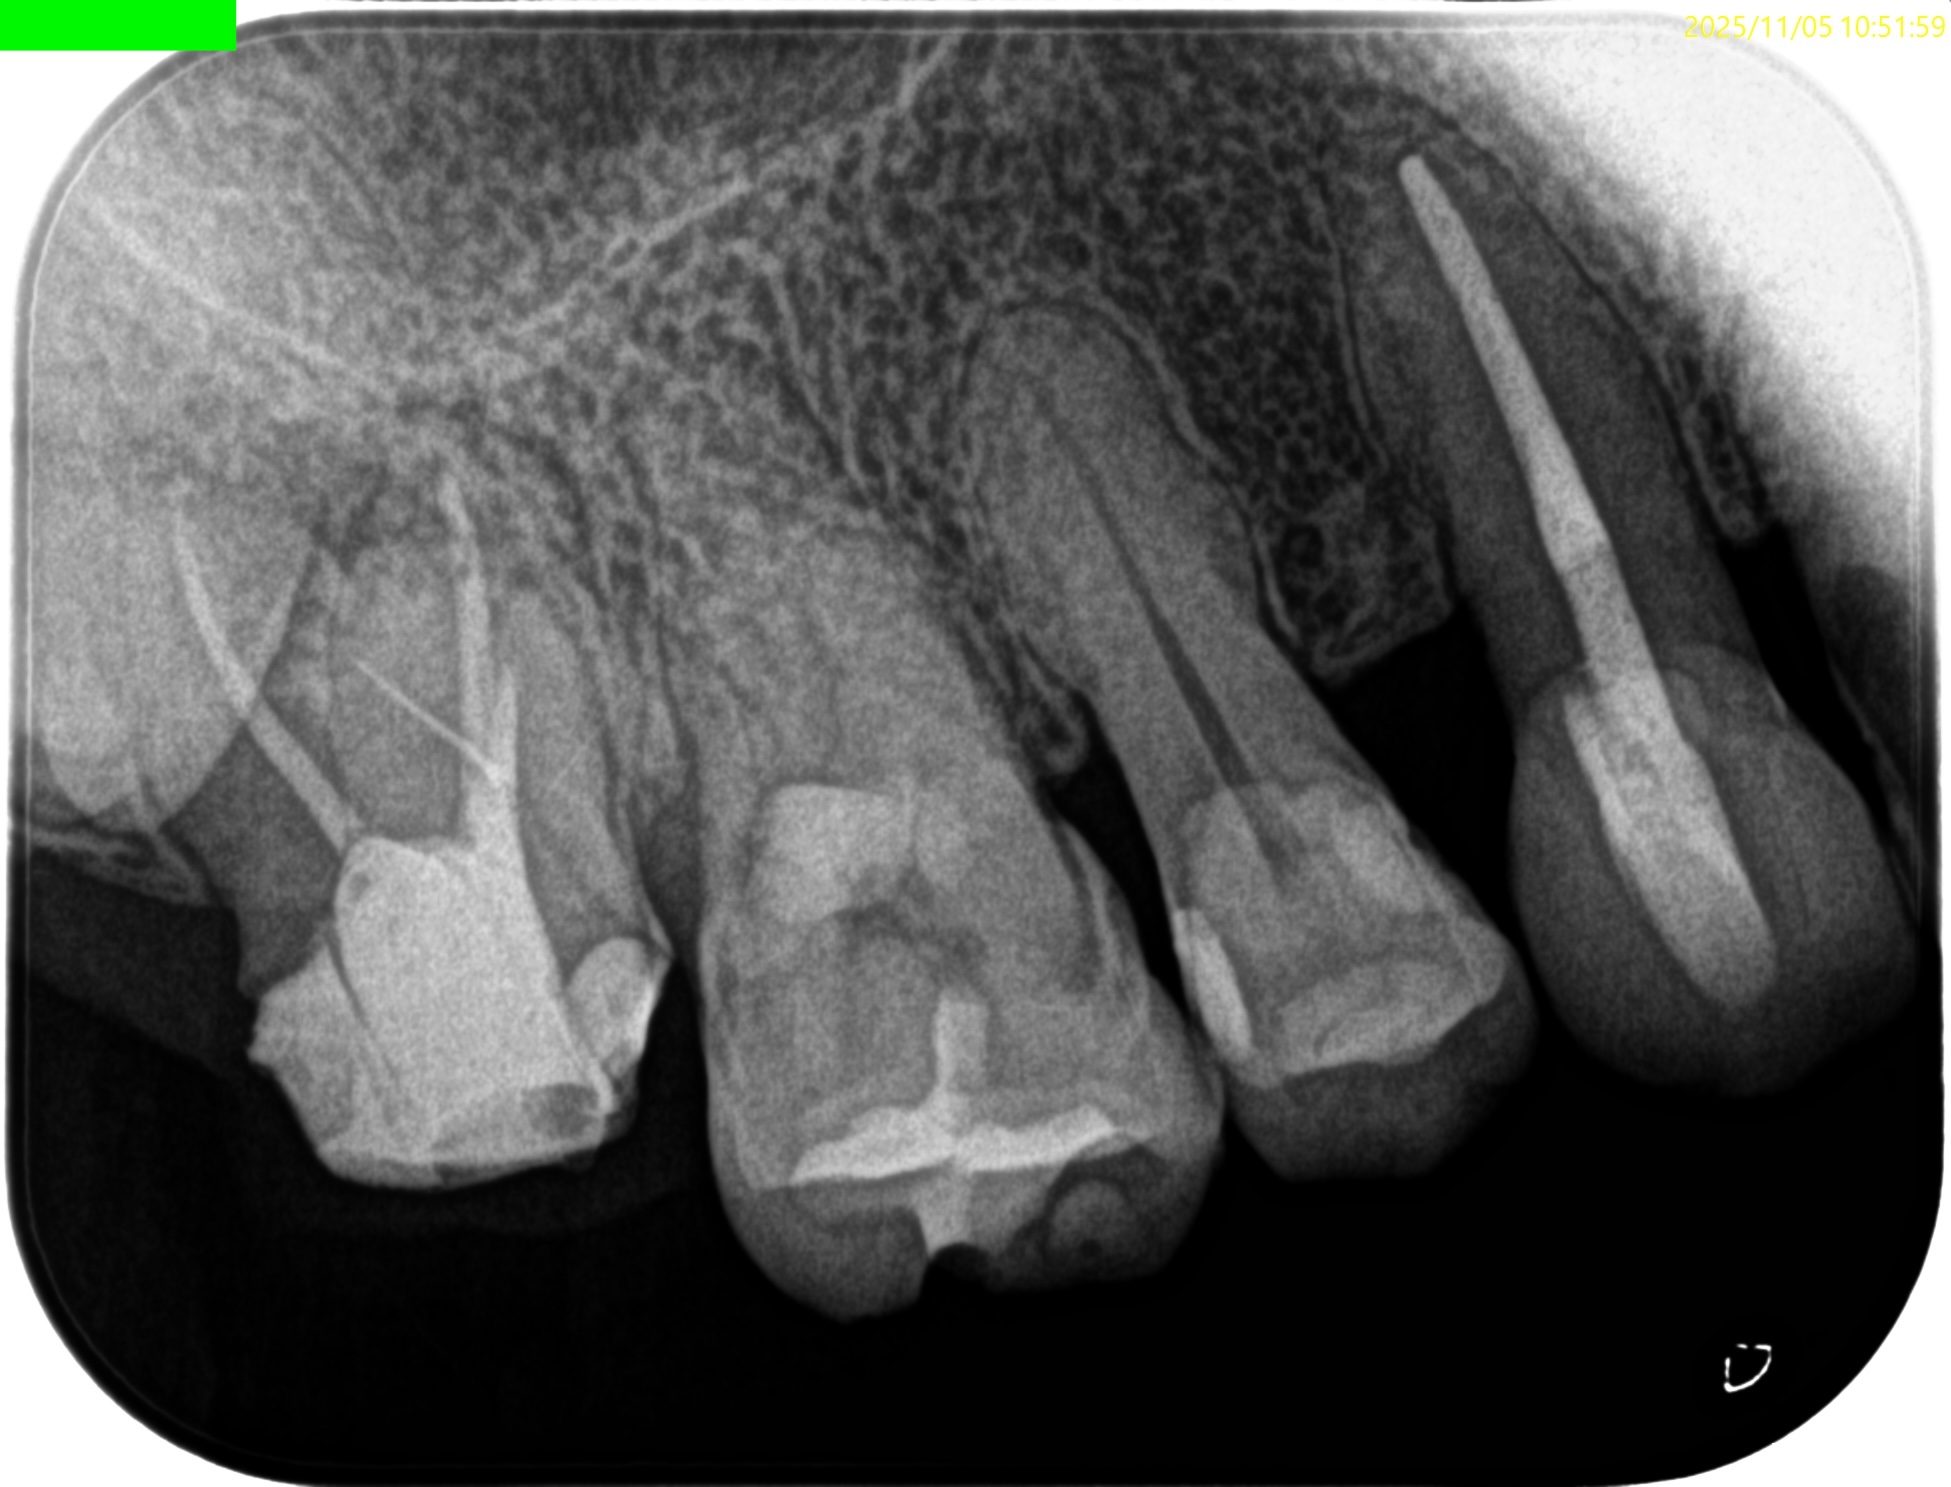

Pre-op Endo test(2025.12.12)

#2 Cold N/A, Perc.(+), Palp.(-), BT(++), Perio Probe(WNL), Mobility(WNL)

依頼された#2には咬合痛と打診痛がある。

主訴と検査項目で出た問題が一致している。

近心根にファイルが折れ込んでいる。

MB

DB

P

Pre-op Endo Diagnosis(2025.12.12)

Pulp Dx:Previously treated

Periapical Dx:Symptomatic apical periodontitis

Recommended Tx: Intentional Replantation